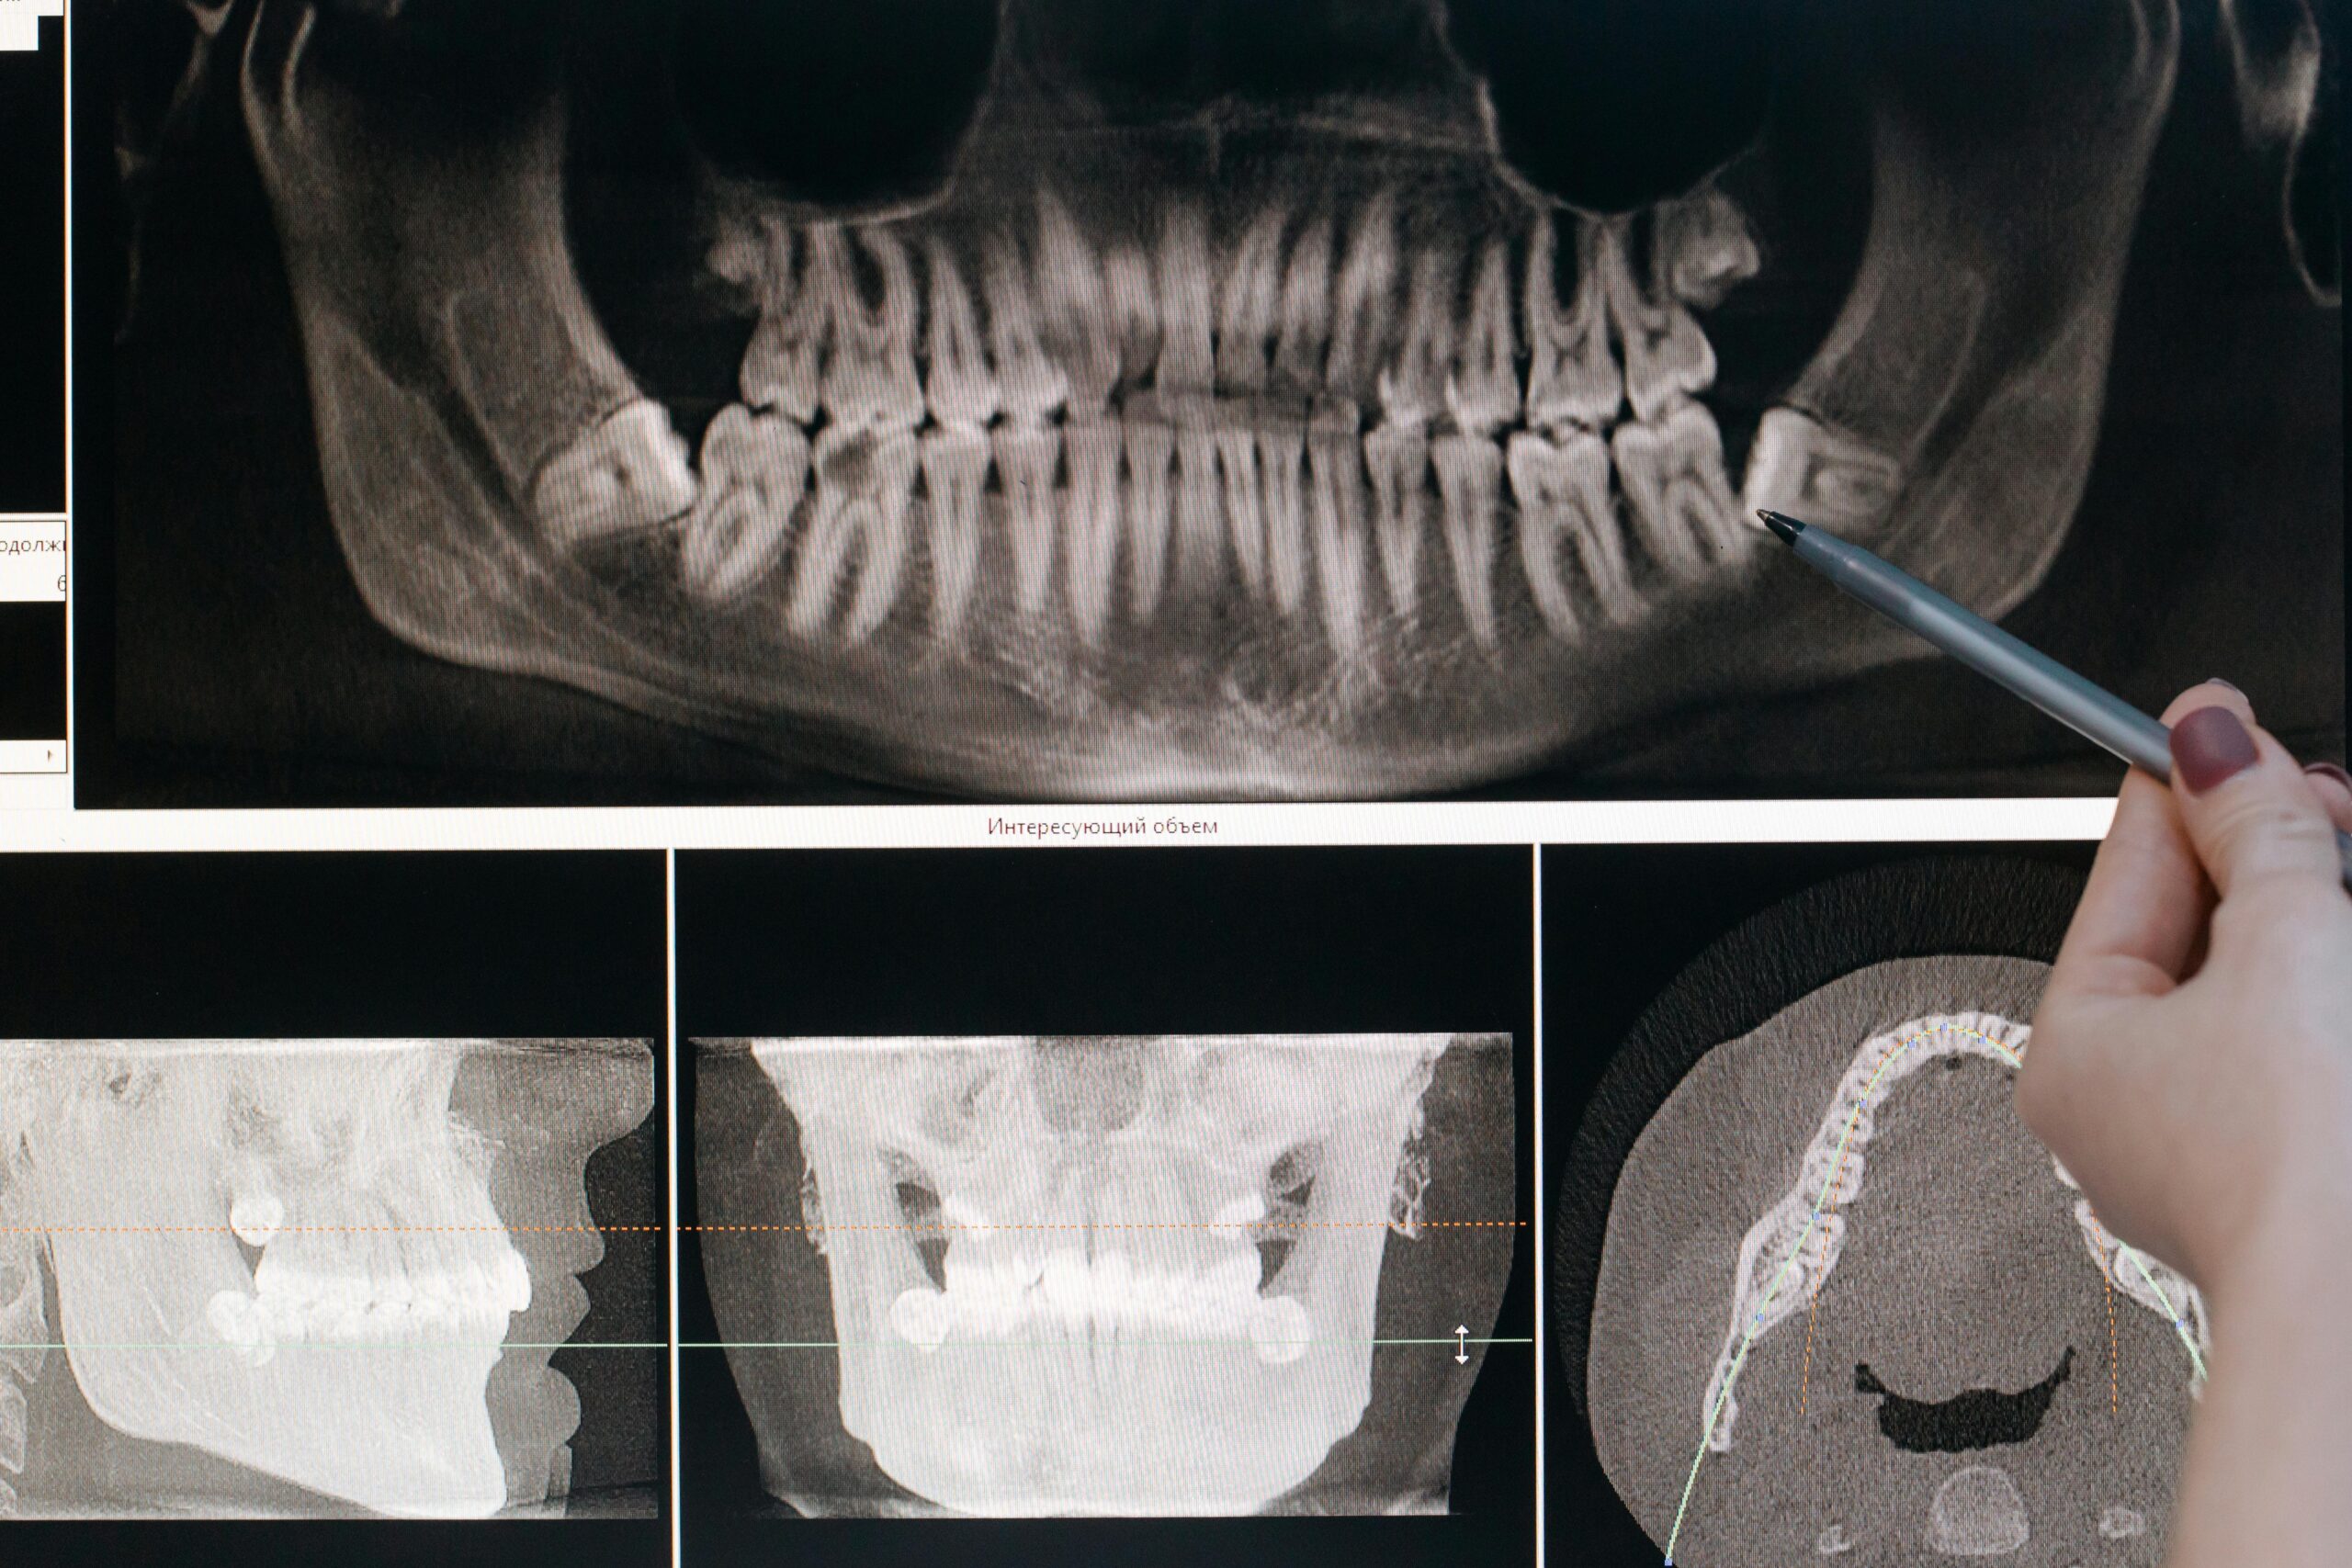

Therapeutic Dentistry: Fundamentals and Techniques Therapeutic dentistry is a foundational branch of dentistry focused on the prevention, diagnosis, and treatment of diseases affecting teeth and soft tissues of the oral…